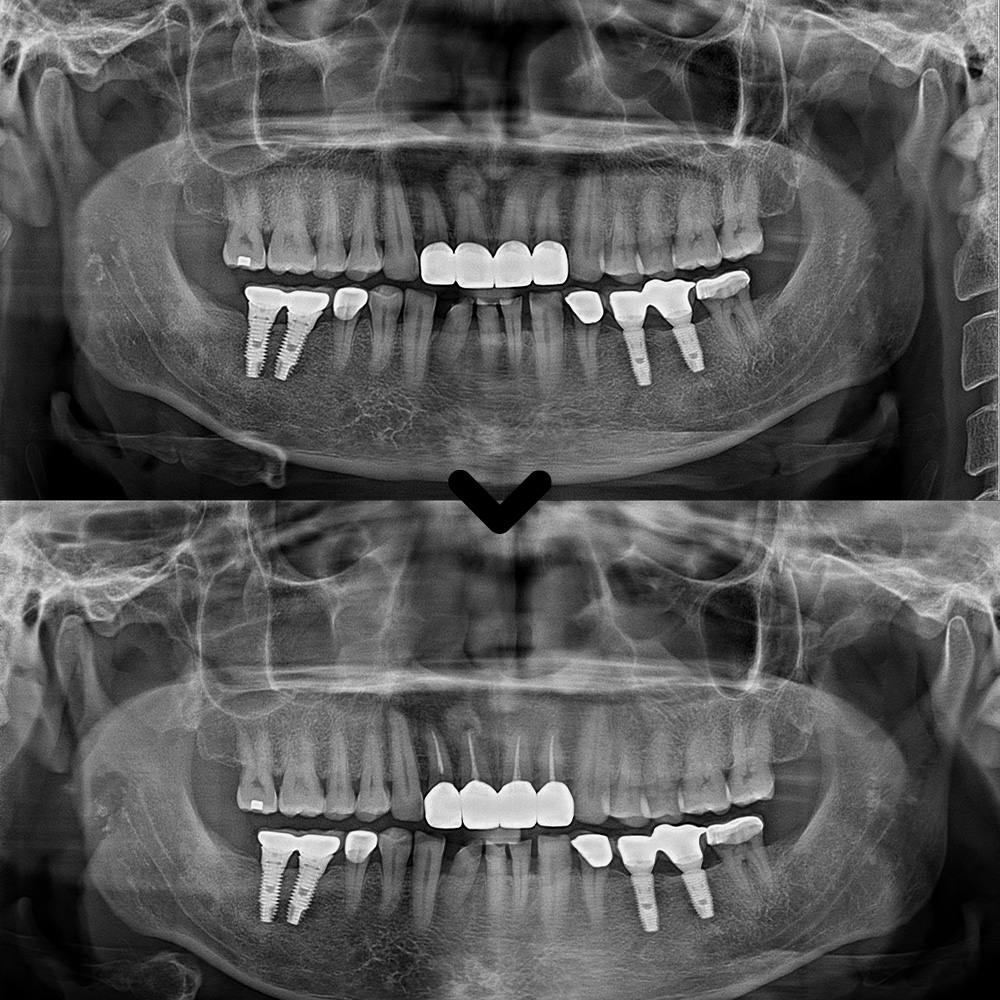

육안으로 확인해 보았을 땐

특별한 이상이 없어

파노라마를 촬영해 보기로 하였습니다.

파노라마를 촬영하고

확인해 보았을 때도,

보철물이 방사선불투과성이라

치아 내부를 정밀하게

확인할 수 없었습니다.

그래서 산성동치과 서울박사치과에서는

해당 브릿지를 제거하여

내부 상황을 확인하기로

환자분과 상의 후 결정하였습니다.